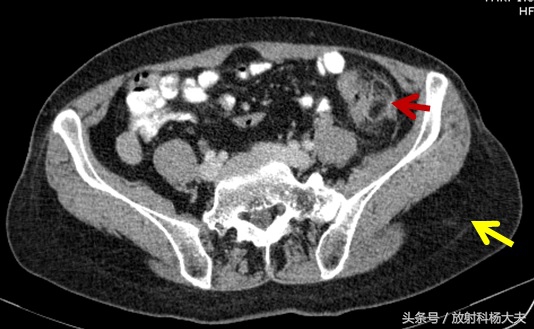

红箭为病变,黄箭为皮下脂肪

这个病CT是最好的检查方法,有一定的特异性。从CT上可以看出来,病变位于肠脂垂区,主要是脂肪密度增高,边界不清楚,仔细分辨,其实局部肠壁是没有病变的。另外,可以看出病人的皮下脂肪很厚,病人很胖!